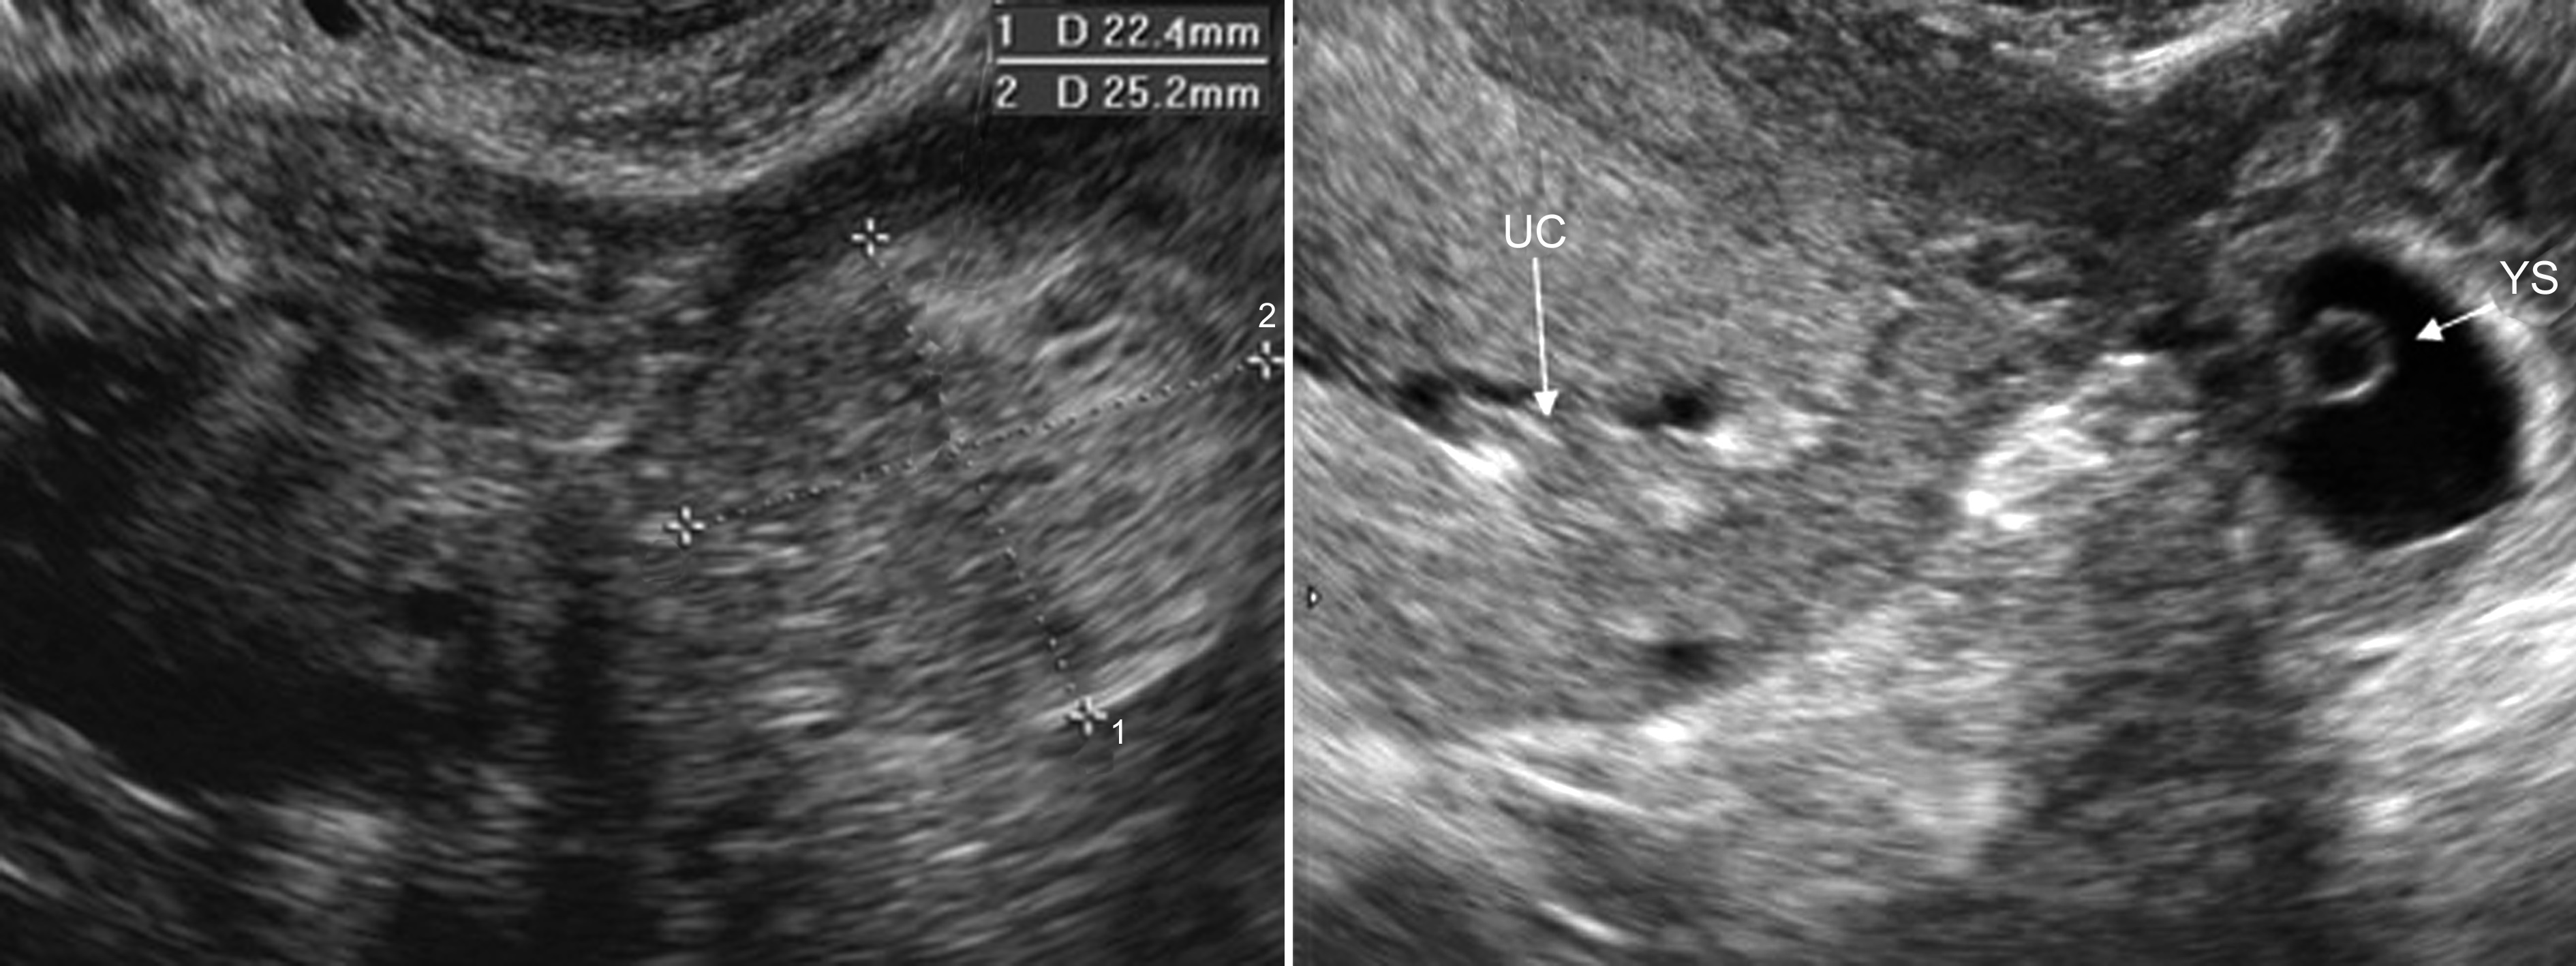

2、附件区团块 输卵管妊娠未破时显示为附件区圆形或椭圆形团块,形态规则,但内壁整齐、清晰(图3)。一般认为,单纯性囊性包块诊断输卵管妊娠的几率不足5%,显示为混合性包块时提示异位妊娠的可能性超过90%。团块内部呈混合性回声或显示典型的孕囊回声(图3,图4),部分(10%~20%)可以显示卵黄囊、胚胎回声或/和胎心搏动(图3,图4), 甚至可以显示胎动。破裂后常可见由妊娠组织、血凝块和周围组织或器官等形成的不规则团块,边缘不清晰、内部回声不均匀,多数区域显示为较低的回声(图5)。

图3 输卵管壶腹部妊娠:A:附件区示局限性回声;B:内部显示无回声及卵黄囊(YS)

图4 输卵管妊娠:右侧附件区显示完整孕囊回声,胚胎2.3mm